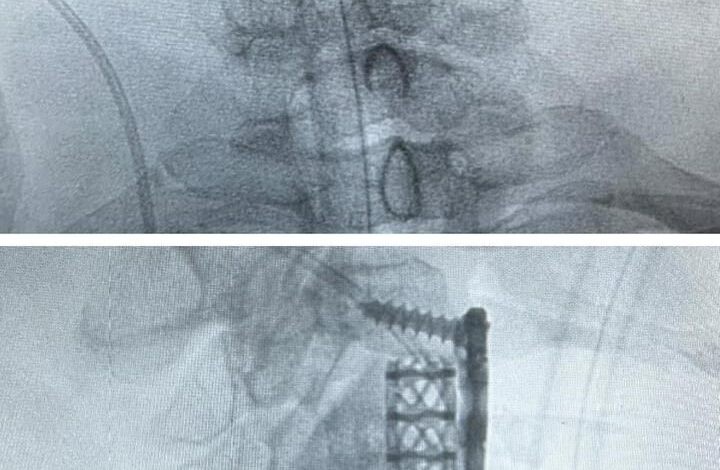

نجح فريق طبي متخصص في مستشفى الملك سلمان عضو تجمع الرياض الصحي الأول من إعادة الحركة لمواطن ستيني؛ يعاني من ضعف وتنميل في اليدين وصعوبة بالتوازن أثناء المشي.

وبعد إجراء الفحوصات الطبية اللازمة تبيّن وجود ضغط على الحبل الشوكي بسبب الغضاريف بين الفقرات الثالثة والرابعة العنقية، ونتوءات عظمية خلف الفقرة العنقية الرابعة، حيث قام الفريق الطبي بقيادة إستشاري جراحة العظام وجراحة العمودي الفقري د. متعب أبو راس بإزالة الغضروف مع استئصال جزئي للفقرة الرابعة؛ لتحرير الحبل الشوكي، ليتم بعدها تثبيت الفقرات بنجاح، حيث تحسنت حالة المريض تماماً بعد العملية الجراحية -ولله الحمد-.

يذكر أن هذه العملية تعد الأولى من نوعها في مستشفى الملك سلمان، كما أنه يجري مختلف العمليات الجراحية الدقيقة والنوعية؛ بتطبيق أفضل معايير الجودة والتميز الصحي عبر تقنيات مستحدثة ووجود كوادر متخصصة.